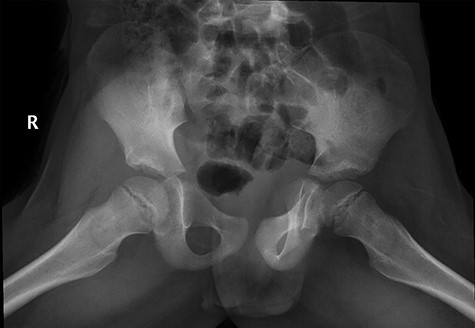

Follow-up of the case showed complete regression of the symptoms. Patient was full weight-bearing and performing daily activities with no pain, straight leg raises up to 90 degrees, Range of motion was fully painless with flexion 120 degrees, while extension, abduction and external rotation were 20, 40 and 35 degrees respectively (Figure 8, 9).

Follow-up X-ray showed regression of the lesion in the form of progression of the dense sclerosis of the defect of the left femur while the right femur neck lesion is barely visible (Figure 10) and advised for watchful waiting.